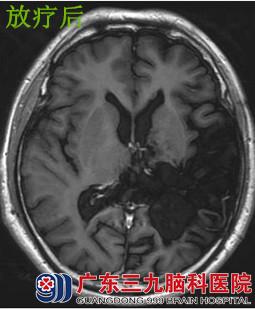

樊某,男性,14岁,1996年6月因“头痛伴恶心呕吐”外院行颅内肿瘤切除术,术后病理:星形细胞瘤Ⅱ级。术后出现发作性意识不清伴肢体抽搐,抗癫痫对症 ,1997年9月复查示肿瘤有复发迹象,遂到广东三九脑科医院肿瘤综合治疗中心进一步检查治疗。当时体征:神清,精神较差,言语欠流利,右上肢肌力Ⅳ级,右下肢肌力Ⅴ-级,右侧肢体肌张力稍高,腱反射亢进。行放射治疗后,残留肿瘤消失。1997至今服用抗癫痫药对症治疗,目前治疗已经17年,此次复查肿瘤无明显复发。